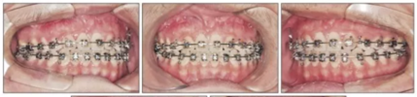

為最小化在青春后期上頜前傾,行骨支抗面弓(面弓聯(lián)合微鈦板[FM-MP])。在15歲1月時(shí)于雙側(cè)上頜骨顴突區(qū)植入兩枚微種植板,4周后加正畸力(500g/邊,與合平面呈30°向下,12-14時(shí)/天),持續(xù)3年5月。